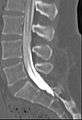

Conventional myelography in oblique projection. You can see the individual nerve root sheaths.

Computed tomography after conventional myelography. The overlap-free representation often allows a more secure assessment. The high density of contrast material may be troublesome in case of insufficient mixing prior to CT.